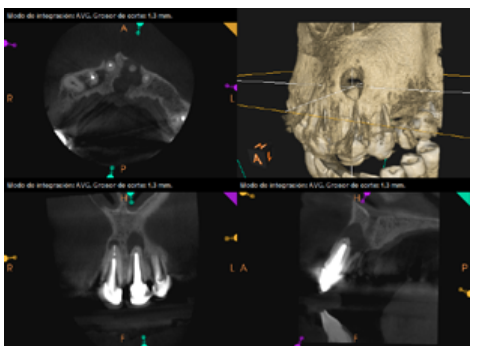

To confirm the endodontic origin and the size of the lesions, tomographic examinations were performed with a slice thickness of 75 microns using CBCT CS8100 (Carestream Dental™), in which radiolucent periapical lesions were observed at the level of 12, 11, 21 (with bicortical involvement), 25 and vestibular roots at 26 (Figures 4 to 8).

Six months later, the patient went for a check-up without any symptoms, both anteriorly and posteriorly. Periapical radiographs showed a decrease in the size of the pre-existing radiolucent periapical lesions (Figures 10 and 11). Given that the lesion on 25 remained to be treated, a control CBCT was performed where improvement at the level of 26 was verified (Figure 12), so microsurgery on 25 was scheduled.

After the microsurgery was performed on 25, the patient had no symptoms and the control tomographies at 12 months (in 25) and at 18 months in the remaining teeth showed regeneration of pre-existing radiolucent periapical lesions on all treated teeth (Figures 13 to 16).